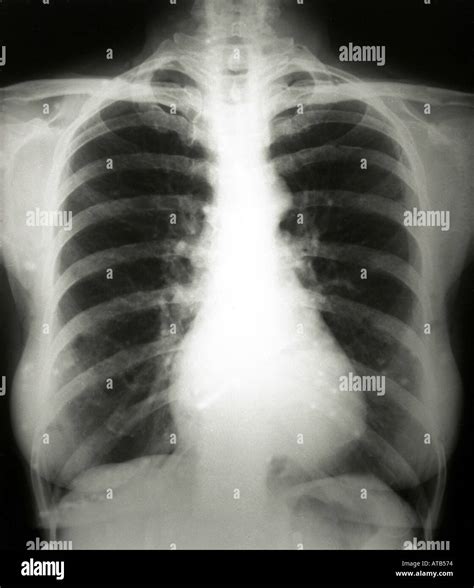

Normal Lung Xray

A chest X-ray, or chest radiograph, utilizes a very small dose of ionizing radiation to produce images of the structures inside your chest. When a radiologist or physician reviews a Normal Lung Xray, they are looking for specific benchmarks that signify health. In a healthy scan, the lungs appear dark, which indicates that they are filled with air. Conversely, dense structures like bones appear white, and the heart typically occupies a standard portion of the thoracic cavity.

• Lung Fields: These should look symmetric and dark, with a fine pattern of branching lines representing the blood vessels.

• Diaphragm: The dome-shaped muscle beneath the lungs should be clearly visible, with the right side typically sitting slightly higher than the left due to the liver.

• Heart Shadow: The heart should occupy less than 50% of the width of the chest, a measurement known as the cardiothoracic ratio.

• Bony Structures: The ribs, collarbones (clavicles), and spine should be visible and intact, showing no signs of fractures or abnormal densities.